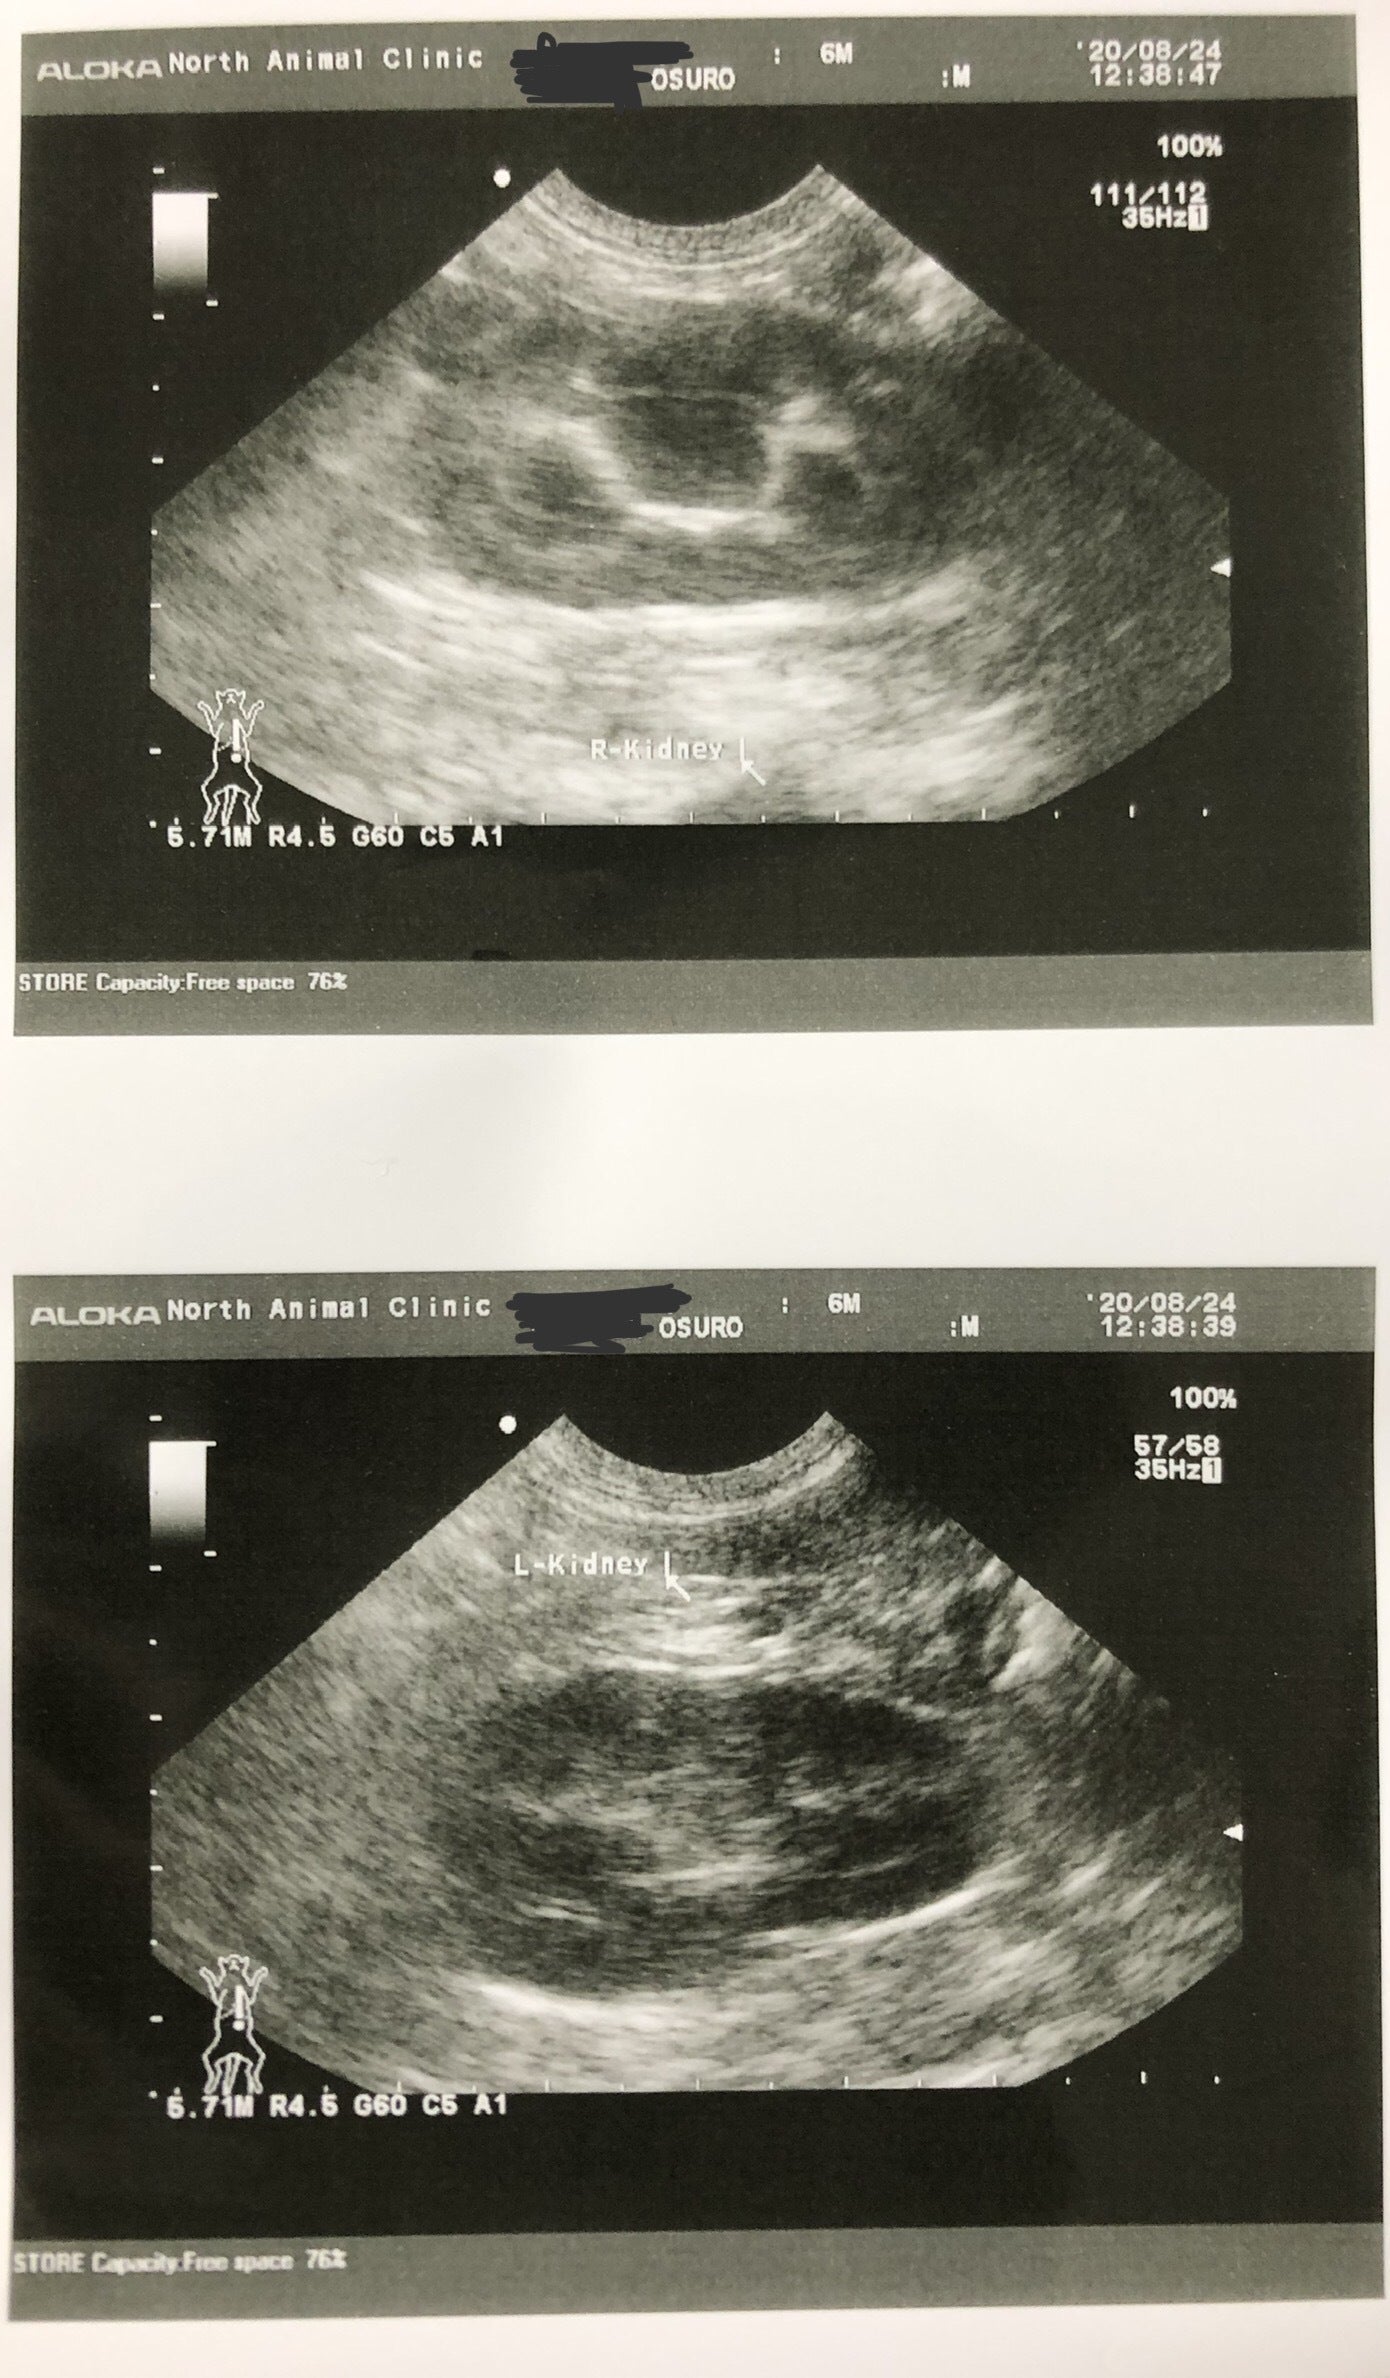

結果は変わっておらず、いろんな病気の検査をすることに。まずは猫エイズ/白血病の検査。こちらは陰性で、続いてエコー検査をしました。するとしこりがあると言われ、どんどん不安が大きくなっていきました。

先生がウイルスの検査をさせてほしいということで、FIPの検査をすることに。このしこりに針を刺して外部検査してもらい、検査結果を1週間待ちました。

診断結果はFIP ドライタイプ 中期でした。ドライタイプは確定診断が難しい場合があり、FIP検査結果が陰性でもFIP症状があり、FIPの治療薬を飲むと効きやはりFIPだったと断定できる場合もあるそうです。